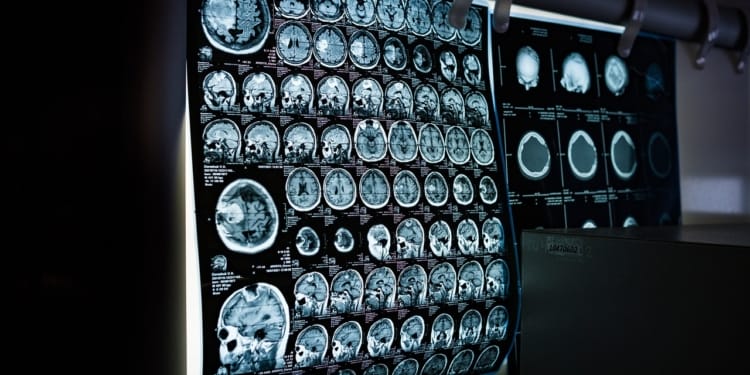

Voor operaties biedt AI een grote verbetering in veiligheid en voorbereiding. Met AI kunnen artsen gedetailleerde scans maken en precies zien hoe ze een operatie het beste kunnen uitvoeren.

Tijdens de operatie kan AI ondersteunen door te waarschuwen voor complicaties of door chirurgische robots aan te sturen voor meer precisie. Dit verkleint de kans op fouten en zorgt voor een sneller herstel van de patiënt.